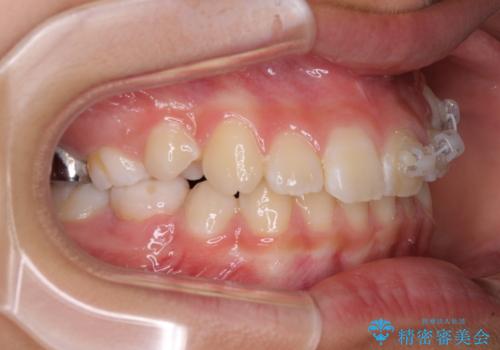

埋もれた犬歯を引っ張り出す 小学生のⅠ期治療

- 小学校での定期歯科検診にて歯列不正を指摘されたとのことで来院された患者様です。

左上の犬歯が低位に埋伏しており、将来八重歯になるリスクが高いと判断されたため、補助装置とワイヤーを用いて犬歯を通常の位置まで移動させることとしました。